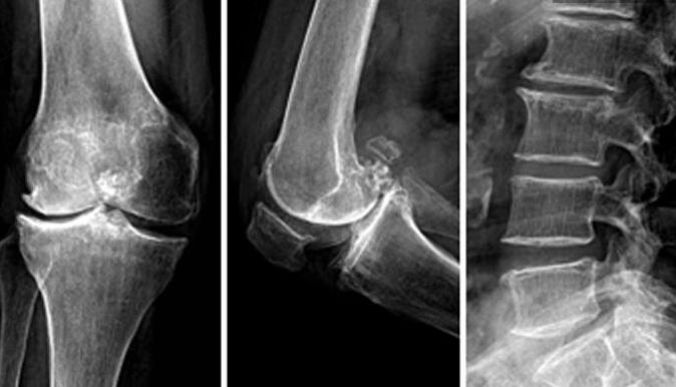

骨关节炎(OA)是发生在滑液关节的一种发展缓慢,以软骨破坏为特征的骨关节疾病,因机械性、代谢、炎症、免疫等因素作用造成,伴有相邻软骨下骨板骨质增生或骨唇形成,可伴有不同程度的滑膜炎症反应,好发于人体负重部位,如膝、髋关节、腰椎等,尤其是膝关节。

根据受累关节病情轻重程度,X线片出现的改变可进行一下分级(Kellgren分级):

0级:正常;

1级:可疑有关节间隙狭窄,似有骨赘;

2级:有骨赘,关节间隙可疑狭窄或无;

3级:有中等骨赘形成、关节间隙狭窄、关节面硬化以及关节似有变形;

4级:有大量骨赘形成、明显关节间隙狭窄、关节面严重硬化以及关节变形。